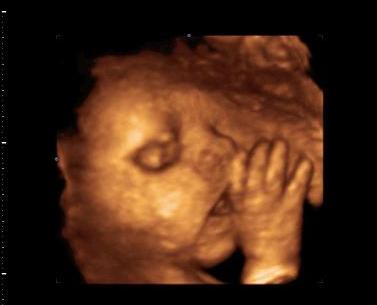

Ezen is a zsinór a sláger itt már puszilgatta :D Kép